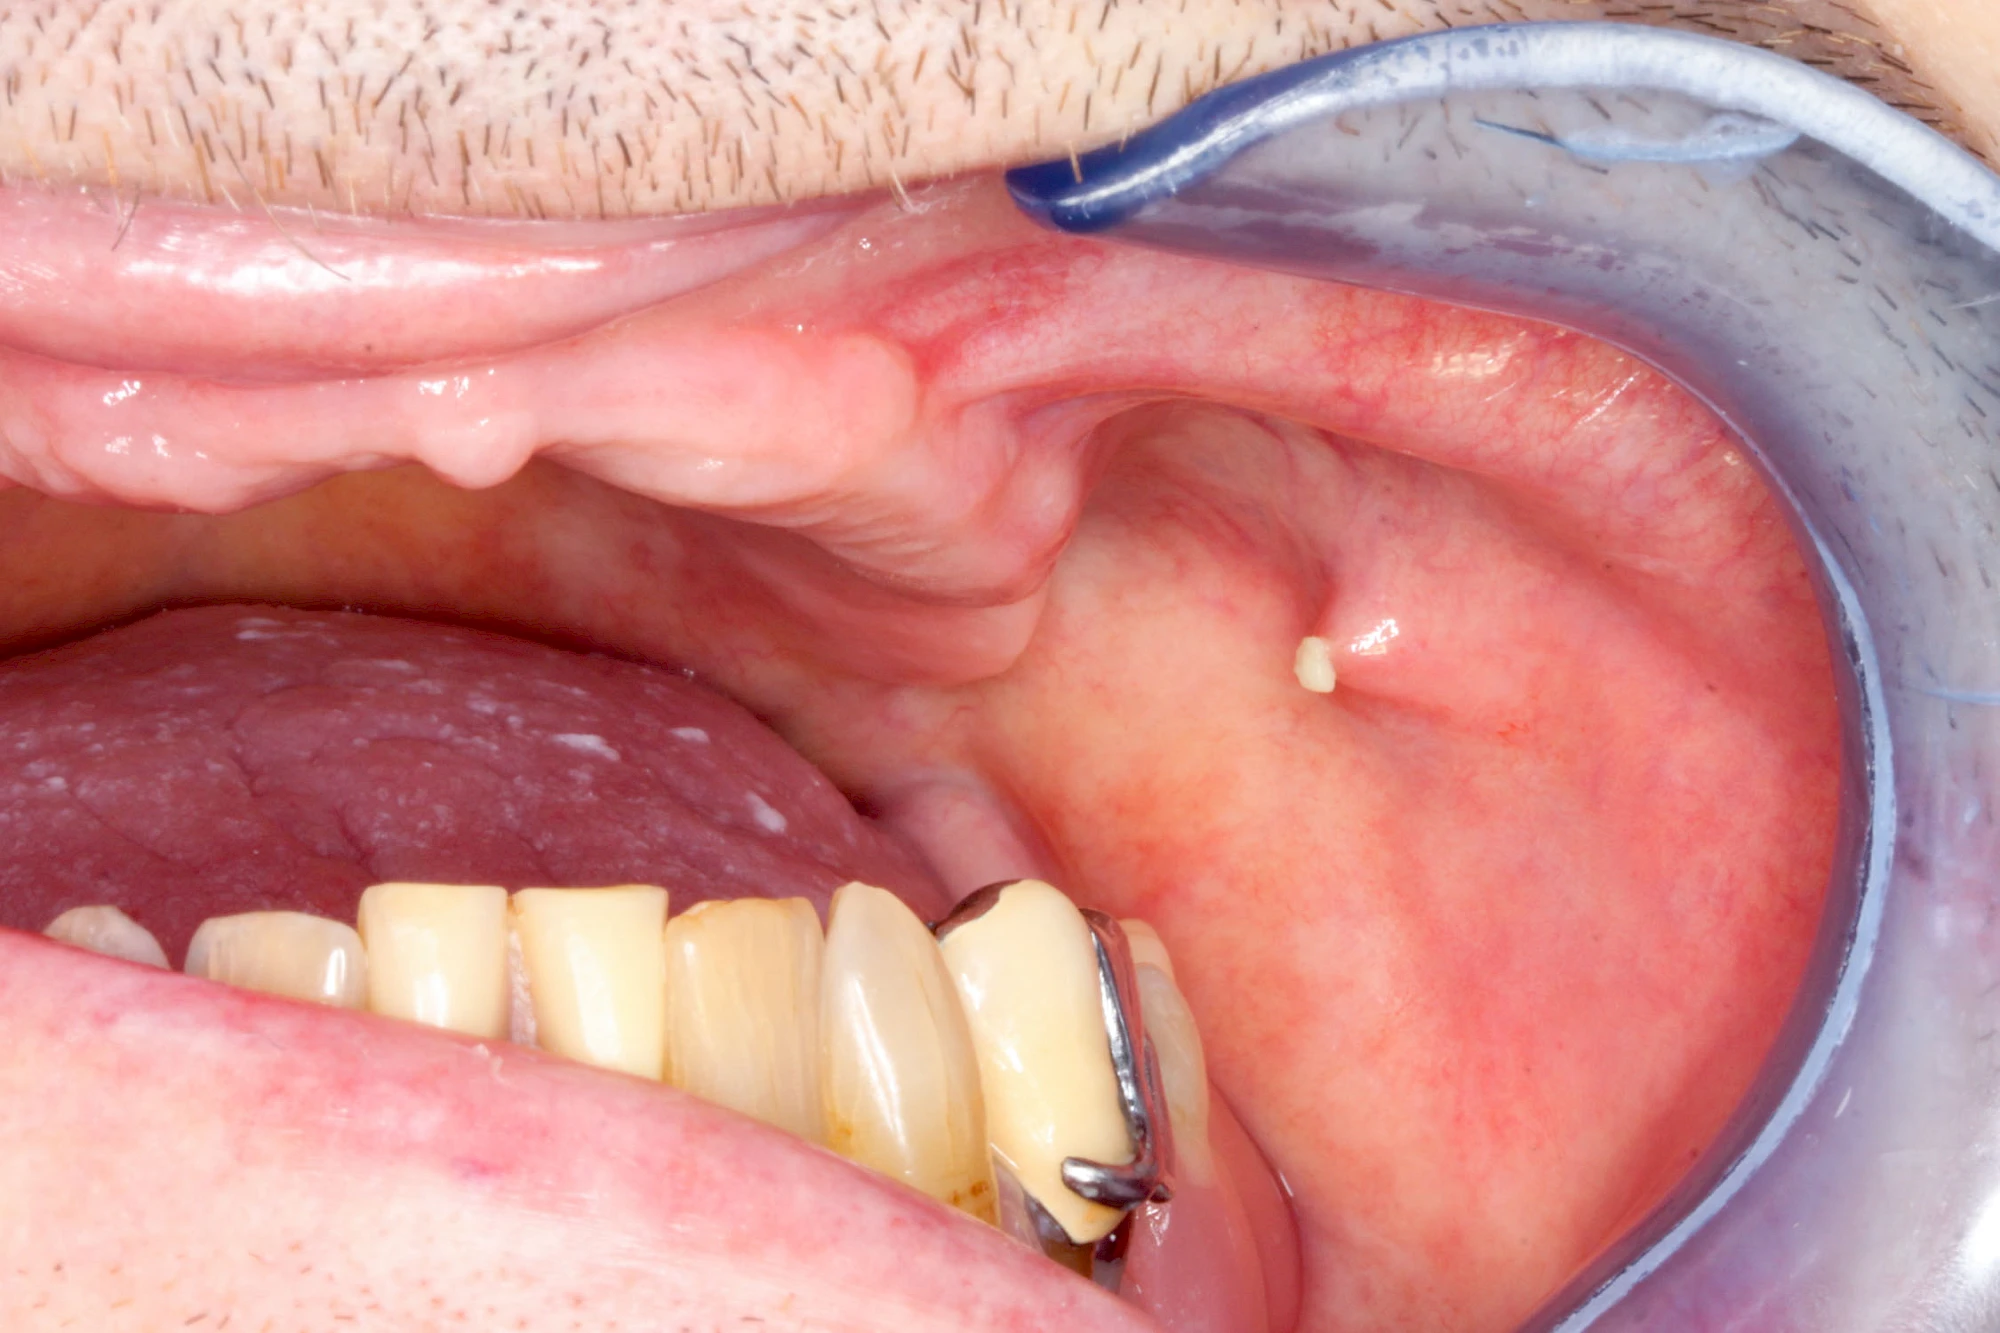

Speicheldrüsenzyste

Eine Speicheldrüsenzyste (Speicheldrüsenretentionszsyte) kann als Schwellung oder Auftreibung meist im Bereich der größeren Ausführungsgängen auffallen, wenn z. B. ein Speichelstein den Speichelfluss behindert. Vor allem bei den Mahlzeiten, wenn der Speichelfluss angeregt wird, nimmt die Auftreibung oder Schwellung schmerzhaft weiter zu. In der Regel ist die Unterkieferspeicheldrüse (Glandula sublinugalis) betroffen. Man spricht dann auch von einer Frosch- bzw. Fröschleingeschwulst (Ranula). Bringt sanftes Massieren der Schwellung bzw. Auftreibung keine Verbesserung, sollte ein Arzt oder Zahnarzt hinzugezogen werden